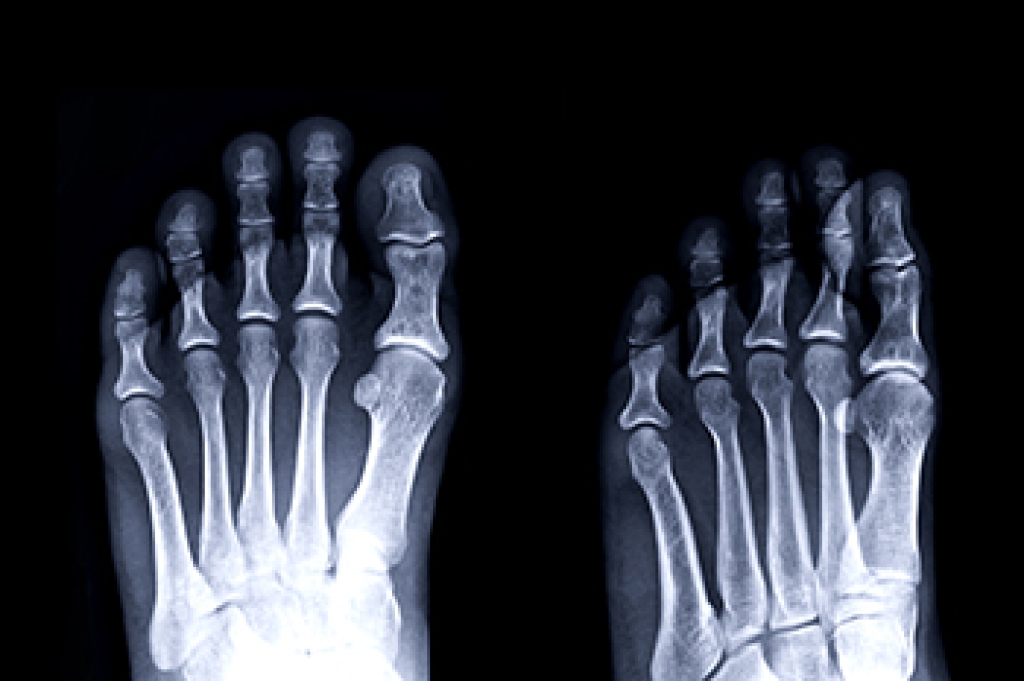

The foot bones are responsible for the mobility of the body, in addition to providing mechanical support for the soft tissues. This is necessary to support the body’s weight while standing and moving. Three categories of bones are in each foot. The tarsals consist of seven bones that are located in the ankle area. The bones in the toes are known as phalanges and connect to the metatarsals, the third group of bones. Additionally, the foot is divided into three areas referred to as the hindfoot, midfoot, and forefoot. Each part of the foot has different functions which work in unison to help you walk and run. The bones in the foot may break when enduring a stress fracture or from a sudden injury. If you would like additional information about the bones in the feet, it is suggested that you confer with a podiatrist who can provide you with the knowledge you are seeking.